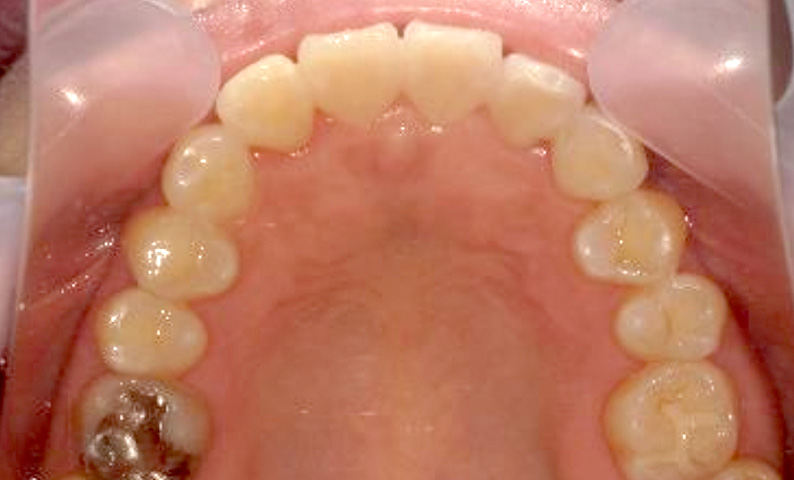

症例_002 上顎だけの部分矯正

治療期間:7ヶ月金額:30万円+税女性前歯のガタガタ上の前歯だけ

| Before | After |

|---|---|

|